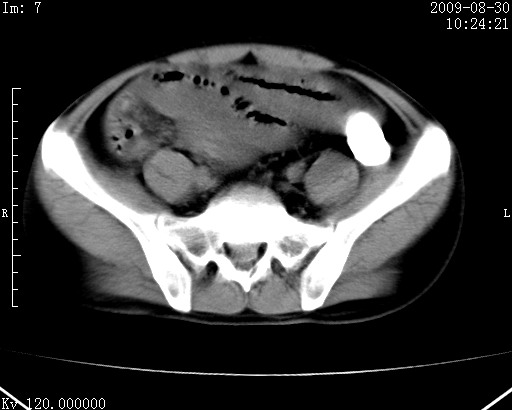

患者唐某,男31岁,已婚,本地务农。

自述入院前两天一次进食较多冷饮之后,出现阵发性上腹部疼痛,次日加剧伴恶心、呕吐,呕吐后症状稍减轻。食欲差。大便每天1-2次,量少,暗红色水样。小便赤。无畏寒、发热、咳嗽等呼吸道症状。无高血压及胃病史。

检查:体温、血压及脉搏正常.皮肤无黄染,浅表无淋巴结肿大。左腹肌紧张,左上腹有压痛,无反跳痛,可触及包块。

生化:钾、钠、氯、钙、ph正常,总胆红素和直接胆红素稍高,空腹血糖稍高。

尿淀粉酶:1256 u/l(正常60-401)。

血常规:wbc 22.4x109/l gr88% ly9.6%其余基本正常。

胃镜:急性胃炎。立位腹平片:未见异常。

下面是ct平扫,降结肠内是对比剂。

术前影像诊断:上段空肠急性缺血性坏死并腹水。建议手术治疗。

术中见上段空肠约70cm长范围坏死,从屈氏韧带远端约10cm处开始。坏死肠管肿胀变形变色,管壁明显环形增厚,部分聚成大肿块,无扭转和套叠。肠系膜上动脉分支内广泛泥沙状血栓。肠切除。

临床诊断:肠系膜上动脉梗塞并急性肠坏死。

开始时我们科也有人认为是套叠,最后统一意见,不考虑肠套。我们看到的“靶征”,“晕圈征”,“双圈征”实际上只是单根肠管的横断面。坏死肿胀后肠壁各层的密度不一样。

左侧腹小肠腔管壁明显增厚,部分内示靶征,走行异常,部分肠系膜绳样改变,肝包膜下及肠间较多液体密度,然梗阻近端肠腔积气不明显。

考虑;肠扭曲伴肠坏死。

有结果了,回顾分析,套叠只会在局部出现同心圆征,不会很长一段肠管都有,还是水肿坏死。